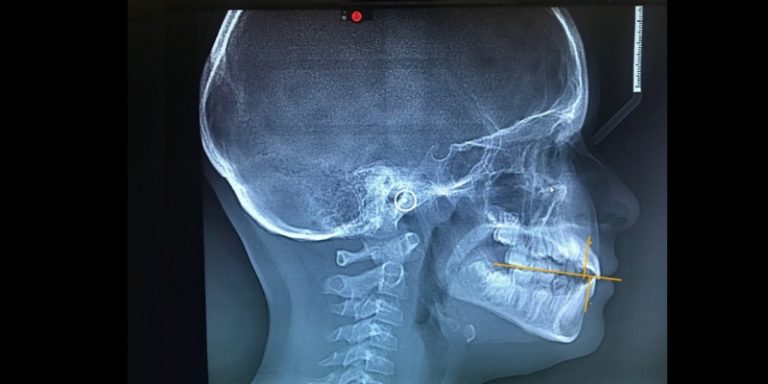

CBCT is a valuable tool for helping dentists find solutions to correct and prevent problematic sleep, esthetics, and occlusal issues and ensure optimal treatment.